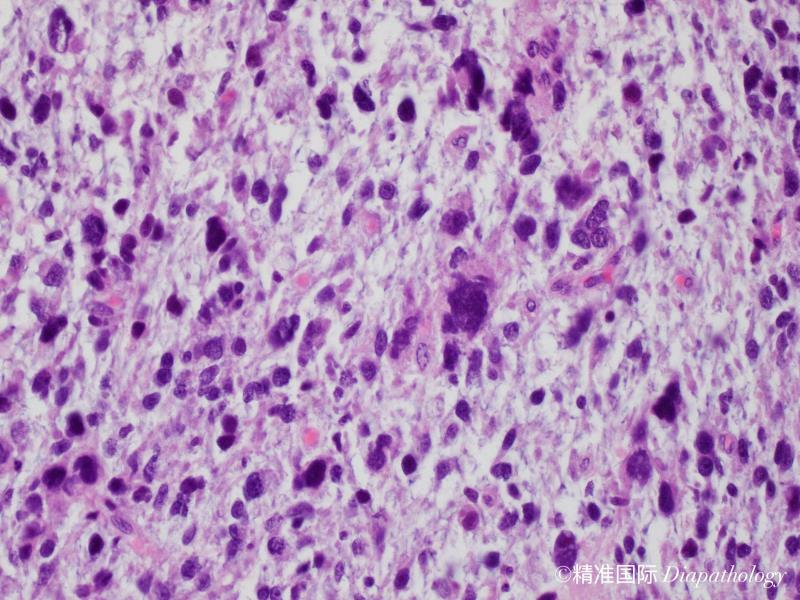

镜下见肿瘤由异型性明显的圆形、多边形深嗜酸性的细胞和一些小的未分化细胞及梭形细胞混合组成;

有些病例见梭形细胞呈束状或不规则状排列,偶尔可呈席纹状排列;部分病例还可见血管外皮瘤样排列;

部分细胞呈蝌蚪状、带状或网球拍状,胞质呈深嗜伊红色,外形不规则,一些细胞大而畸形,具深伊红色胞浆,这类细胞具有诊断价值;

部分区域可见瘤巨细胞或多核巨细胞,类似多形性未分化肉瘤;